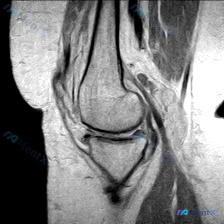

临床怀疑半月板异常但MRI单一切面正常?这个鉴别思路值得复盘

临床提示:可疑半月板异常,提供单张膝关节矢状位T1加权MRI影像

- 图像质量:标准矢状位T1WI序列,信噪比良好,解剖结构显示清晰,无明显运动伪影

- 骨骼结构:股骨、胫骨骨髓信号符合成人正常脂肪骨髓表现,无异常低信号区;关节软骨连续平滑,无明显缺损剥脱;关节间隙正常,无大量积液

- 韧带结构:后交叉韧带走行、信号、连续性均正常;前交叉韧带在此切面显示不全,未见明显异常增粗或信号改变;髌韧带、股四头肌腱形态信号均正常

- 半月板结构:本切面显示的半月板前后角形态清晰,为正常三角形低信号,无穿透关节面的异常高信号,结构完整

- 其他结构:髌下脂肪垫信号均匀,周围软组织无明显异常

影像初步结论:该单一切面T1加权影像未见半月板、骨质、韧带的明确病理改变。